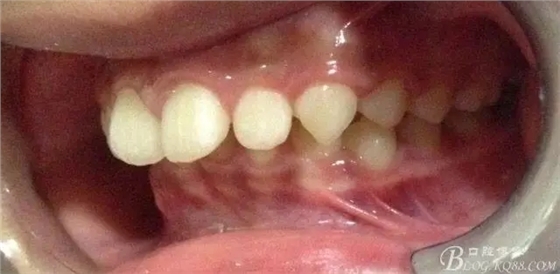

術(shù)前側(cè)貌,下合后縮還算明顯,正面照有點(diǎn)看不出的樣子!